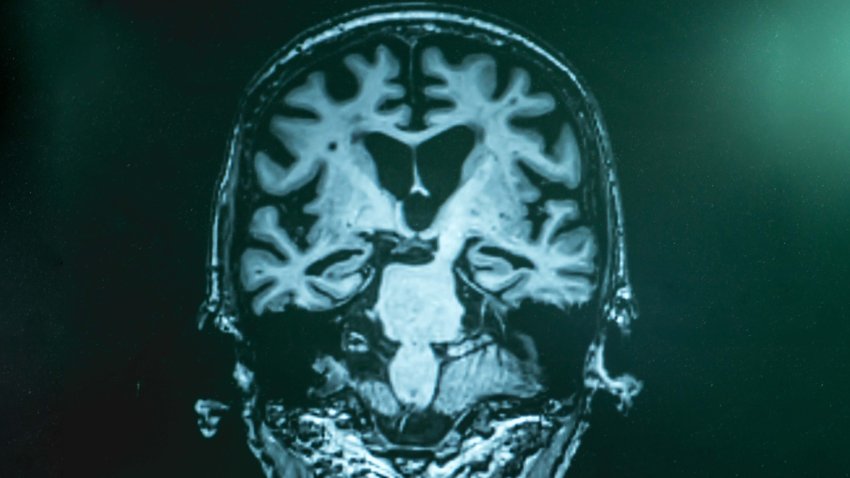

El uso prolongado de antiácidos podría aumentar el riesgo de demencia, según estudio

El estudio se suma a la lista de afecciones ya vinculadas a estos medicamentos, entre las que se incluyen derrames cerebrales, cardiopatías y enfermedades renales.

Fármaco experimental muestra eficacia contra el alzhéimer, según un estudio

Los datos se presentaron en una reunión sobre Alzheimer en San Francisco y se publicaron en The New England Journal of Medicine. Los reguladores estadounidenses podrían aprobar el medicamento en enero.

Estudio demuestra que la mala calidad del sueño provoca un alto riesgo de desarrollar esta enfermedad

Se ha analizado los datos de 1,168 adultos mayores de 50 años, incluyendo biomarcadores de la enfermedad de Alzheimer.